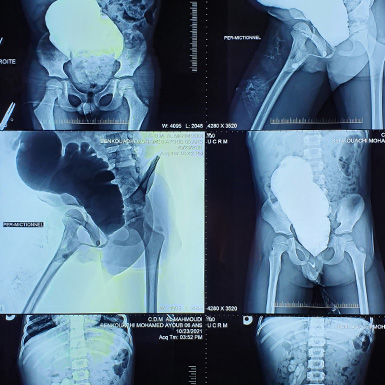

تعدّ الموجات فوق الصوتية للكلية (Échographie rénale) مفيدة بشكل خاص لاكتشاف أي تشوّه خلقي في المسالك البولية، إذ إن وجود مثل هذه التشوهات يزيد من خطر الإصابة بعدوى المسالك البولية.

ويُفضَّل أن تبدأ فحوصات الكشف عن التشوهات الكلوية بالموجات فوق الصوتية، بعد فترة من انتهاء نوبة العدوى، لضمان دقة النتائج وتجنّب تأثير الالتهاب الحالي على الصورة التشخيصية.

التشوهات الخلقية للكلى والمسالك البولية (CAKUT): مثل ارتجاع البول (Reflux Vésico-Urétéral )، والذي يُعد أحد الأسباب الشائعة جدًا لحدوث التهابات المسالك البولية لدى الأطفال.